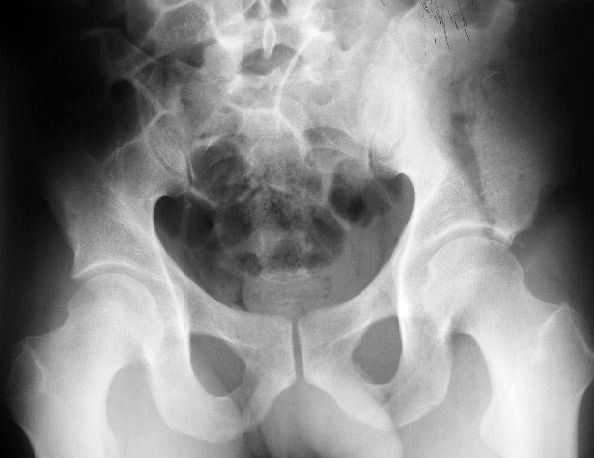

Поступил пациент после кататравмы (упал с высоты 4м). После обследования установлен Ds: Сочетанная травма. ЗТГК перелом 5-6 ребер справа. Ушиб левого леогкого. Оскольчатый перелом крыла подвздошной кости слева, со смещением. в экстренном порядке выполнена операция о/синтез таза стержневым аппаратом. Снимки прилагаются. Пациент со 2-го дня стал ходить без костылей. Из анамнеза жизни у пациента имеется гепатит В и С, с 1998г. употребляет наркотики (героин 1г в день нормальная доза). На контрольных снимках таза в аппарате смещение отломков сохраняется, да еще и стержни сломались. Подскажите ув.коллеги, как поступить в данной ситуации: оставить все как есть или добиваться репозиции в аппарате, или планировать на открытую репозицию. На сегодняшний день пациент стабилен, по анализам компенсирован. Принимает героин по другому справиться не может. С ув. Андрей

Отказ от оперативного лечения, учитывая невозможность соблюдения пациентом постельного режима, может привести к формированию ложного сустава подвздошной кости, а, возможно, и к трансалярной грыже (редкость, но бывает, тема уже обсуждалась на форуме).

Если отбросить социальные аспекты, инфекцию и наркоманию то несомненно лучше опереировать.

вариант 1 в свежем случае репозиция и трансфрактурная фиксация через проколы под ЭОПом (сгибание бедра облегчит репозицию)

Вариант 2 нет винтов - закрытая репозиция, фиксация аппаратом но на стороне повреждения вместо стержней 5-10 трансфрактурных спиц введенных через гребень

Вариант 3 Нет Эопа, срок больше 10 дней - подвздошный доступ, репозиция щипцами (можно крокодилами за винты) фиксация двумя пластинами по внутренней стороне на разных уровнях + винты прансфрактурно. (если больной очень активный для нейтрализации мышц живота можно небольшой аппаратик набросить сверху).